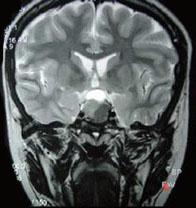

问题 男,47岁,视物模糊数月,头痛、恶心、呕吐3天,行MRI检查如图,最可能的诊断为()

选项 A.颅咽管瘤 B.脑膜瘤 C.垂体瘤并出血 D.蛛网膜囊肿 E.表皮样囊肿

答案 C